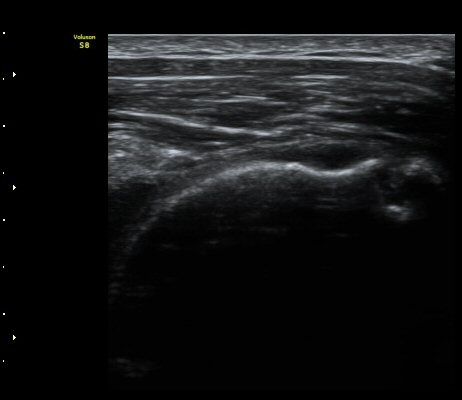

°ß°©ÇÏ±Ù°Ç Á¾´Ü¸é°Ë»ç¿Í Ⱦ´Ü¸é°Ë»ç¿¡¼­ °ß°©ÇϱٰÇÀÇ ÀüÃþÆÄ¿­ ¼Ò°ßÀ» º¸ÀÓ(»çÁø 5, 6)